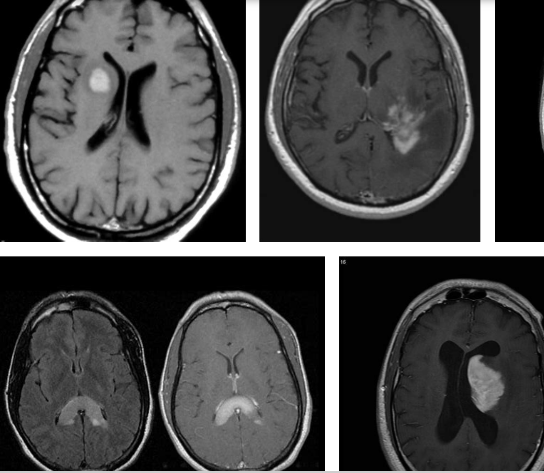

Localization of Brain lymphomas

Primitive lymphomas of the central nervous system are non-Hodgkin (NHL) lymphomas that appear in the brain or in the spinal cord. These are mostly B-type lymphomas. The most common forms of Cerveausont lymphoma are those that affect:

Areas around the cerebral ventricles (periventricular lymphoma);

Central grey nuclei;

The callus body (located between the cerebral hemispheres).